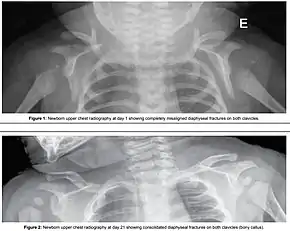

Shoulder dystocia is when, after vaginal delivery of the head, the baby's anterior shoulder gets caught above the mother's pubic bone.[3][1] Signs include retraction of the baby's head back into the vagina, known as "turtle sign".[1] Complications for the baby may include brachial plexus injury, or clavicle fracture.[2][1] Complications for the mother may include vaginal or perineal tears, postpartum bleeding, or uterine rupture.[3][1]

Typically the procedures are performed in the order listed and the sequence ends whenever a technique is successful.[10] Intentional fracturing of the clavicle is another possibility at non-operative vaginal delivery prior to Zavanelli's maneuver or symphysiotomy, both of which are considered extraordinary treatment measures. Pushing on the fundus is not recommended.[1]

- Intentional causing clavicular fractures, which reduces the diameter of the shoulders that requires to pass through the birth canal;[2]